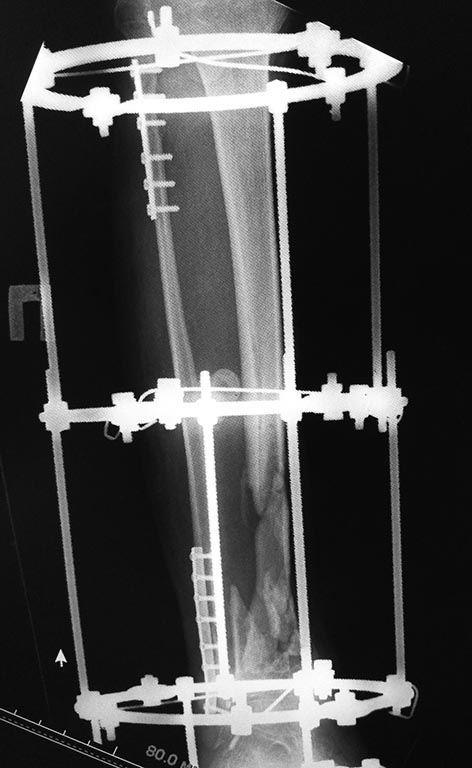

Добрый вечер, уважаемые коллеги.  Представляю Вам пациента после,

кататравмы ,  которая случилась в декабре 2016г. Длительное время

лечился в стационаре, множество повреждений поэтапно было оперировано.

Что касаемо голени, перелом был закрытый.

Выполнена открытая адаптация отломков б/берцовой кости, комбинированный

остеосинтез костей голени. Рана зажила первично. В настоящее время

пациент передвигается самостоятельно при помощи костылей и из всех

повреждений, вопрос с голенью остался не решенный. Представляю вам

снимки первичные при поступлении и голень в аппарате на сегодняшний день.